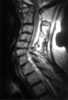

Postoperative arthritis